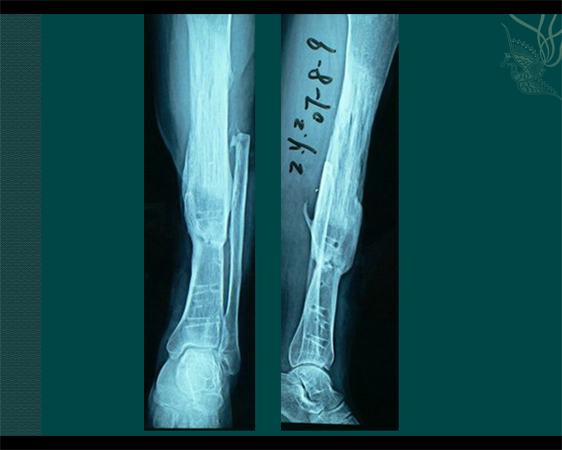

Bone transport